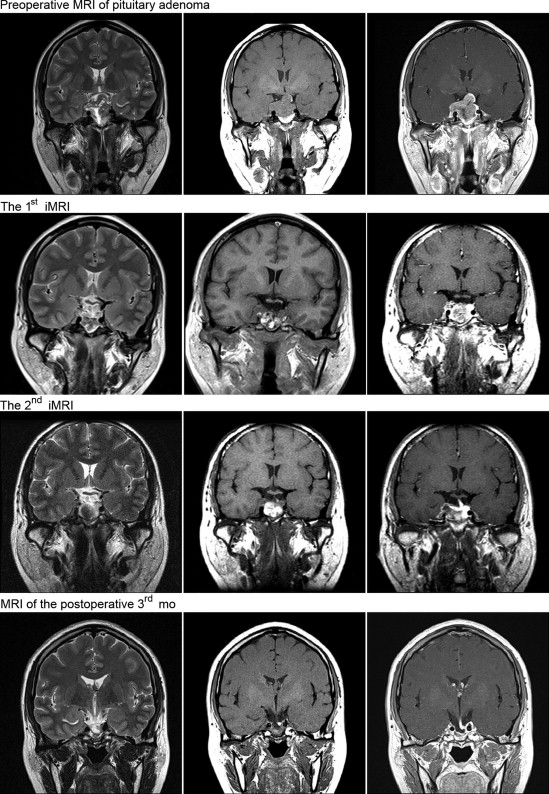

The extent of tumor resection needed was determined by iMRI examination. Residual tumor was identified in 12 cases, among which nine cases required further resection. We did not perform further resection in the remaining three cases because the tumor had extensively invaded the cavernous sinus, sphenoid sinus, and clivus, with hard or tough texture, and the extent of resection had reached the preoperative expectation. Among the nine cases that required further resection, iMRI rescanning confirmed complete resection in six cases, and subtotal resection in the remaining three (the tumor invaded the cavernous sinus and surrounded the carotid artery, and the resection range had achieved the expectation). Overall, 24 cases achieved complete tumor resection, and six cases achieved subtotal resection. The complete tumor resection rate increased from 60% to 80% (Figure 1 ;  Figure 2).

Resection of a large invasive pituitary adenoma under the assistance of ...

Figure 1.

Resection of a large invasive pituitary adenoma under the assistance of intraoperative magnetic resonance imaging (iMRI) using the nasal-transsphenoidal approach.